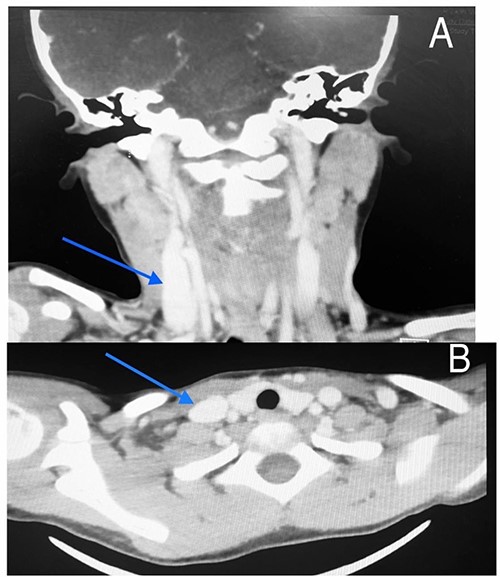

Imaging examination of the patient was done by performing CT with contrast and US. US Doppler showed a right dilated internal jugular vein during coughing and the valsalva maneuver (Fig. 5). CT showed a wide right internal jugular vein (Fig. 6). Both cases managed conservatively with follow-up and no surgical intervention as they did not have any complication or cosmetic concerns.

CT scan of the second patient in coronal view (A) and axial view (B) with blue indicate internal jugular phlebectasia.